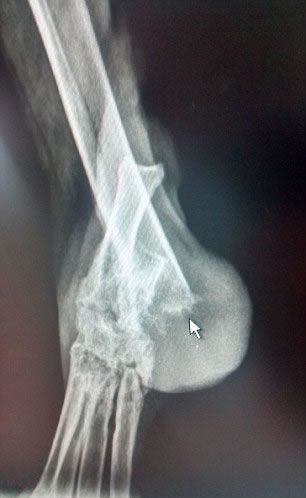

Elmo, un perro de 10 años, fue hallado con la cadera dislocada, los hombros y las piernas rotas e incluso varias pequeñas fracturas en las piernas cuando fue rescatado en un cementerio de Wirral.

Los veterinarios también dijeron que todos los huesos del cuerpo de Elmo se habían roto en algún momento de su vida - recuerda que los perros tienen un total de 319 huesos. A medida que las lesiones ocurren tienen diferentes fechas de calcificación, se ha descartado la hipótesis de que Elmo hubiera sido atropellado.